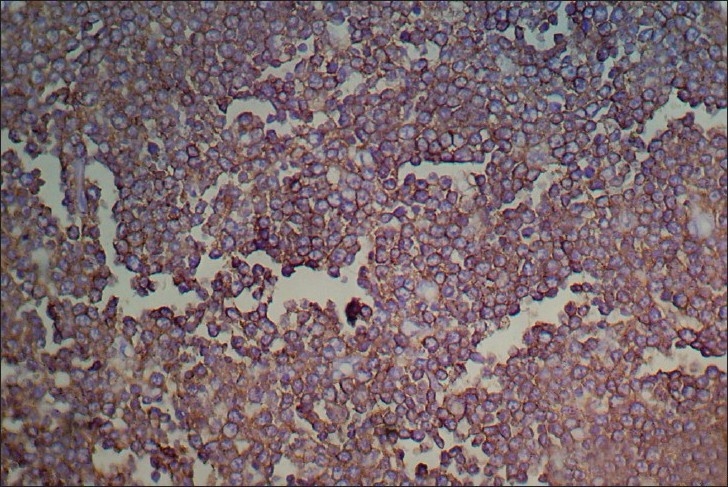

Histology of the lesions showed classical Burkitt lymphoma (BL) in one case with diffuse sheets of small tumor cells having round to oval nuclei and several prominent basophilic nucleoli. The chromatin was coarse and nuclear membrane was thick. This case showed a prominent starry-sky pattern [Figure 1]. The tumor was positive for B-cell marker CD20, negative for CD3, Tdt and showed a high proliferative index [Figure 2]. In the second case from terminal ileum, the cells were larger and more atypical with few binucleate forms. This tumor also showed a very high proliferative index and was diagnosed as atypical Burkitt. The remaining four cases showed histology of a diffuse large cell lymphoma and were positive for B-cell marker CD20 and negative for CD3 [Figure 3].

| Fig. 3 Photomicrograph showing CD20 positive cells in a case of diffuse large B-cell lymphoma (CD20 immunostaining, ×400)